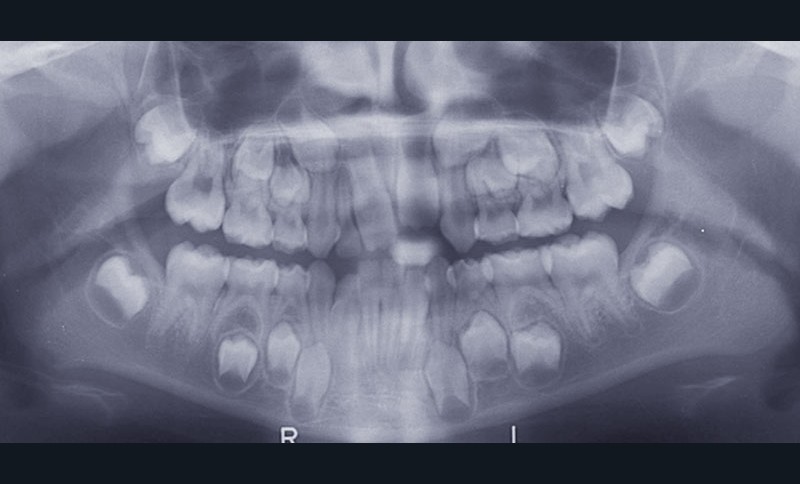

Cette jeune patiente de 6 ans se présente à la consultation avec une panoramique de dépistage révélant l’agénésie des deux incisives latérales permanentes (fig. 1).